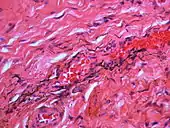

| Amalgam tattoo in upper labial sulcus in an edentulous individual, left behind after teeth have been lost/extracted | |

If necessary, the diagnosis can be confirmed histologically by excisional biopsy, which excludes nevi and melanomas.[3]: 138 If a biopsy is taken, the histopathologic appearance is:[1]

- Pigmented fragments of metal within connective tissue

- Staining of reticulin fibers with silver salts

- A scattered arrangement of large, dark, solid fragments or a fine, black or dark brown granules

- Large particles may be surrounded by chronically inflamed fibrous tissue

- Smaller particles surrounded by more significant inflammation, which may be granulomatous or a mixture of lymphocytes and plasma cells